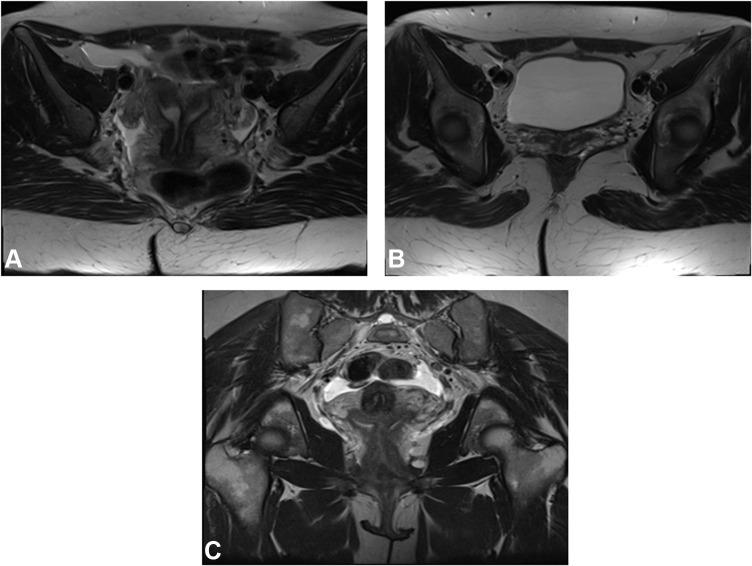

Variable mullerian anomalies were found among patients with multiple frequencies. Mullerian agenesis and hypoplasia were found in 12 patients (19%) and 16 patients (25%), respectively. Uterus didelphys was found in 5 patients (8%). Twelve (19%) patients had septate uterus, while 8 (12.5%) had a bicornuate anomaly. Unicornuate uterus was present in 7 patients (11%). Isolated vaginal anomaly was diagnosed in 4 patients (6%). Renal/urinary tract imaging was available for 27 (42%) patients, and accompanying urinary tract anomalies were noted in 10 of them (37%). Few ovarian and other extra-renal anomalies were observed.

MRI could efficiently delineate the mullerian anomalies regardless of their complexity. Most of these anomalies were more efficaciously categorized by the ESHRE and the new ASRM systems, compared to the originally widely used AFS system. The new ASRM classification was found to be more practical as it is a modification of the original AFS system, using drawings with clear descriptions instead of symbols. This is particularly helpful in the radiological era, saving time and effort.